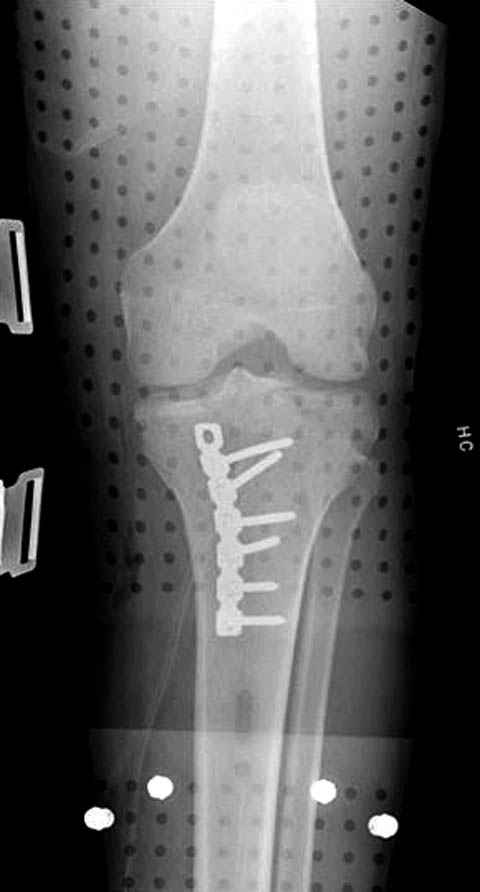

Трудно поверить, что разрекламированная Ортопедическая школа Восточной Украины позволяет такие странные снимки? На прямом снимке сохранен общий контур плато, но не известна судьба импрессии суставной поверхности. На полубоковой?, оставлен без репозиции задне-медиальный отдел, и навряд ли после такой фиксации можно удовлетвориться результатом.

Такая ситуация характерна для многих, когда принимается ошибочное решение, т.е пытаются фиксировать одним имплантом переломы двух мыщелков. Латеральная пластина приемлема только для тех случаев, когда сохраняется интактным медиальный диафизарный кортекс и отсутствует фрагментация на верхушке медиального перелома.

Представленные снимки не информативны, нужны отдельные качественные снимки коленного сустава и голени без ротации.